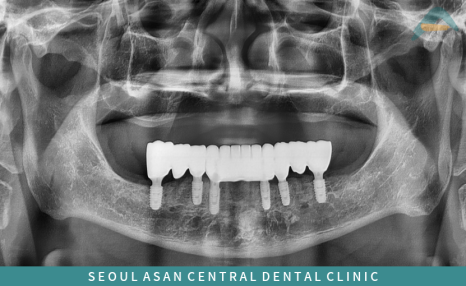

성남치과 서울아산센트럴에서는

발치 이후 아래턱의 경우

전체 틀니를 통해 일시적인 기능 회복은 가능하지만,

장기적인 사용 과정에서 발생할 수 있는

불편 요소를 함께 고려하여

보다 안정적인 유지와 기능 회복을 기대할 수 있는

아래턱 전체 임플란트 치료를

치료 계획으로 설정할 수 있습니다.